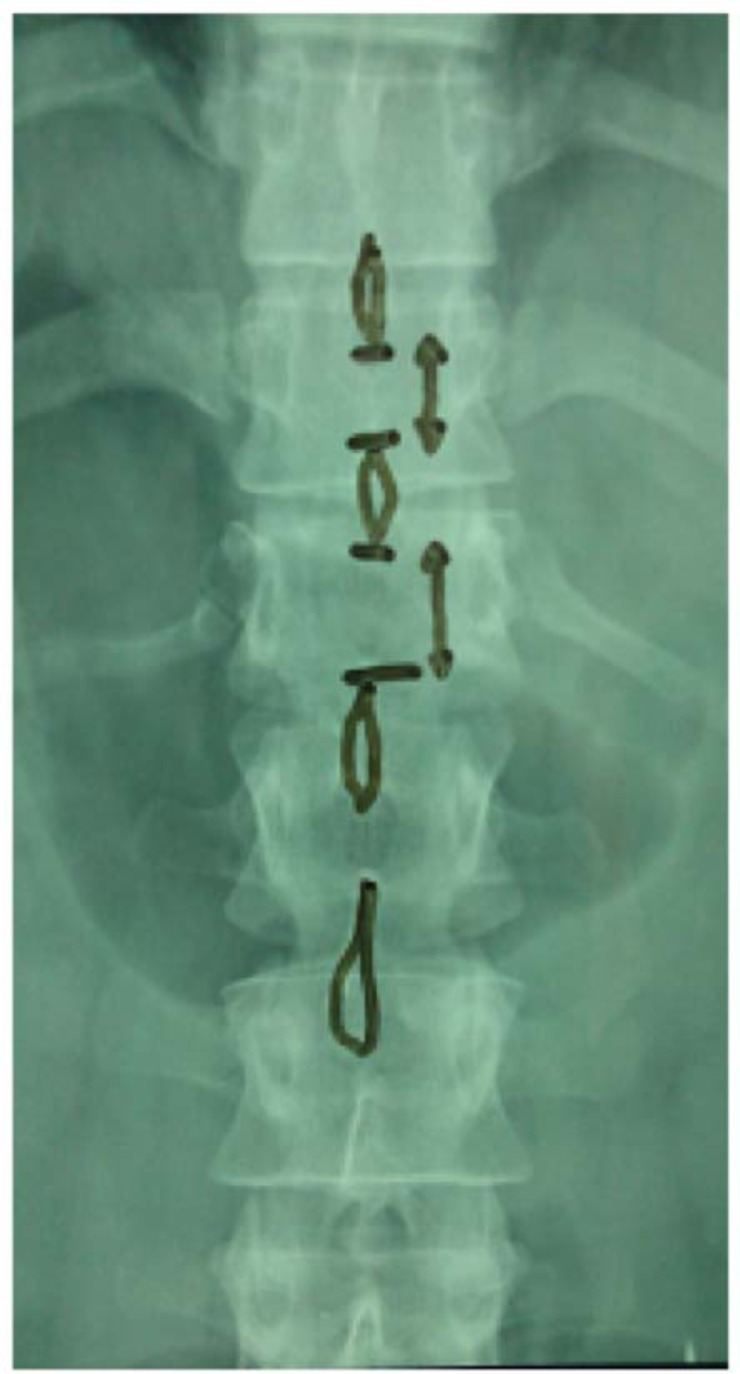

Upon admission, palpation revealed tenderness at the thoracolumbar region. His neurologic examination was normal with no motor or sensory deficit of the lower and upper limbs. Ultrasonography was performed to exclude blunt abdominal concomitant injuries. Simple radiographic evaluation of the cervical spine, thorax and pelvis did not demonstrate associated injuries. Radiographs (Figs. 1, 2) and CT scans (Fig. 3) of the thoracolumbar spine revealed a transverse fracture at the level of T12. The CT scan further demonstrated a split of the posterior elements, progressing anteriorly into the vertebral body. Conservative treatment was decided and the patient, following an initial period of bed rest, was mobilized wearing a thoracolumbar orthosis. Appropriate antithrombotic prophylaxis with low molecular weight heparin was administered, until full ambulation was achieved. The patient was followed up with serial thoracolumbar radiographs for the first 6 weeks of ambulation and later on, in one month intervals. The thoracolumbar orthosis was applied for three months. At the 5th month follow-up, he was pain free with radiographic signs of mild vertebral kyphosis. Upon completion of treatment, he returned successfully to pre-injury levels of daily activity, without any impairment.

Fig. (2). Anteroposterior (AP) radiograph demonstrating increased interspinous distance at the level of injury.